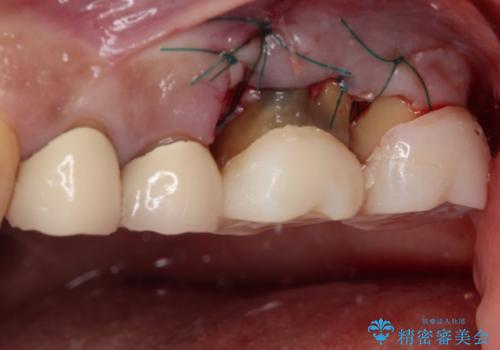

左側は骨欠損が著しいことが予想されるため、骨造成術並びに歯肉移植術を併用することとしました。

歯肉縁下にまで虫歯が及んでいたため、歯冠長延長術を行い、清掃性の改善を試みます。